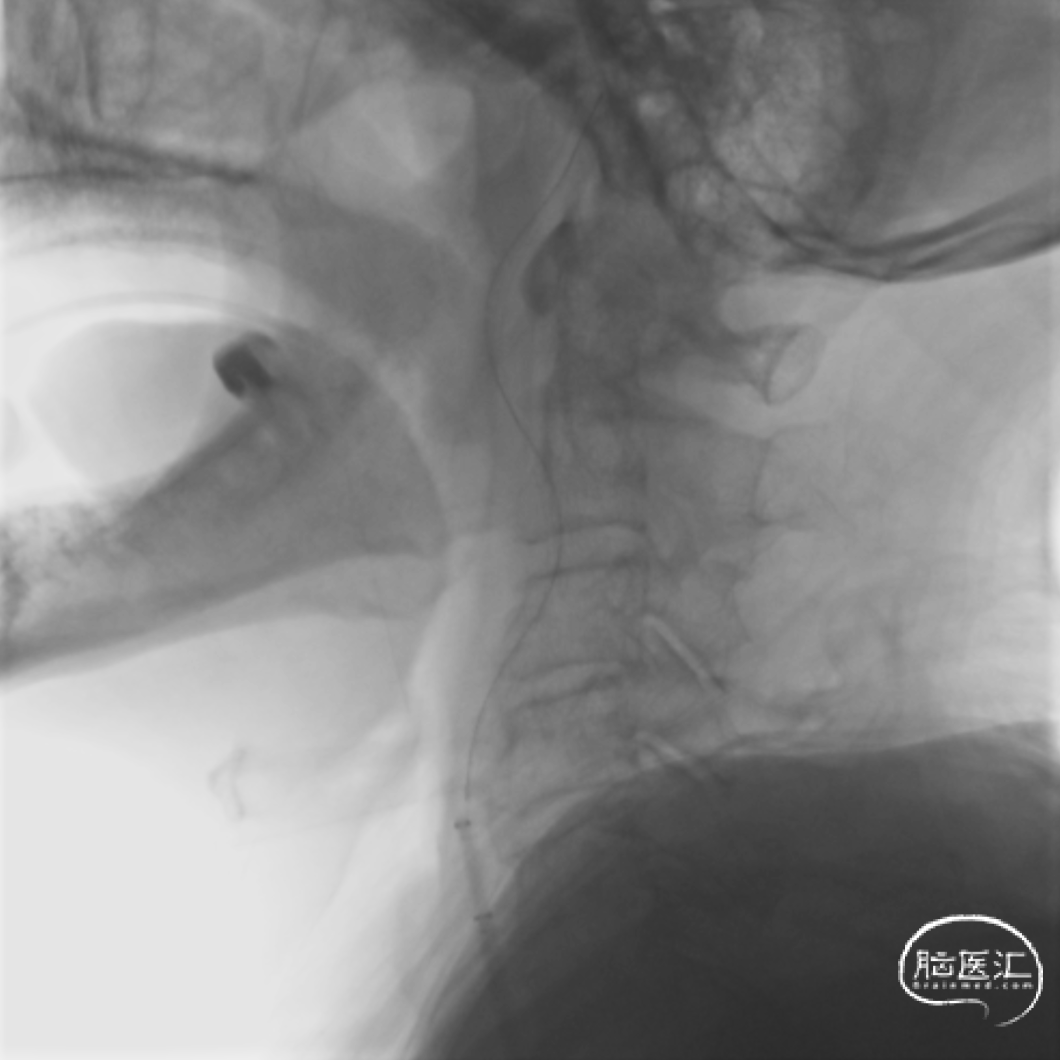

3型主动脉弓,用Mani管超选至右颈总动脉,用260cm加硬泥鳅导丝交换出,在泥鳅导丝导引下,用125cm的多功能管将6F Infinity长鞘置于右颈总动脉,提供稳定支撑。

Infinity 长鞘 提供稳定支撑

在Synchro2微导丝及微导管引导下,Catalyst7抽吸导管顺利到达颈内动脉末端。